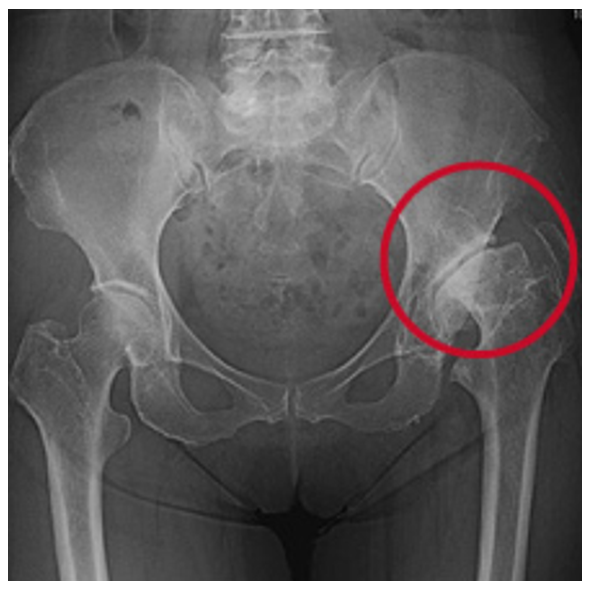

レントゲンで見ると一次性は、正常な股関節が長い年月や股関節の使い過ぎによって軟骨が消耗して変形性股関節症が発症します(図7)。二次性は、元々臼蓋形成不全により体重がかかる部分が限られており早期なら軟骨が消耗し変形性股関節症になります(図8)。

図8. 二次性の変形性股関節症

乳児期の股関節の脱臼や股関節の発育が悪いこと(臼蓋形成不全)が原因で起こる。